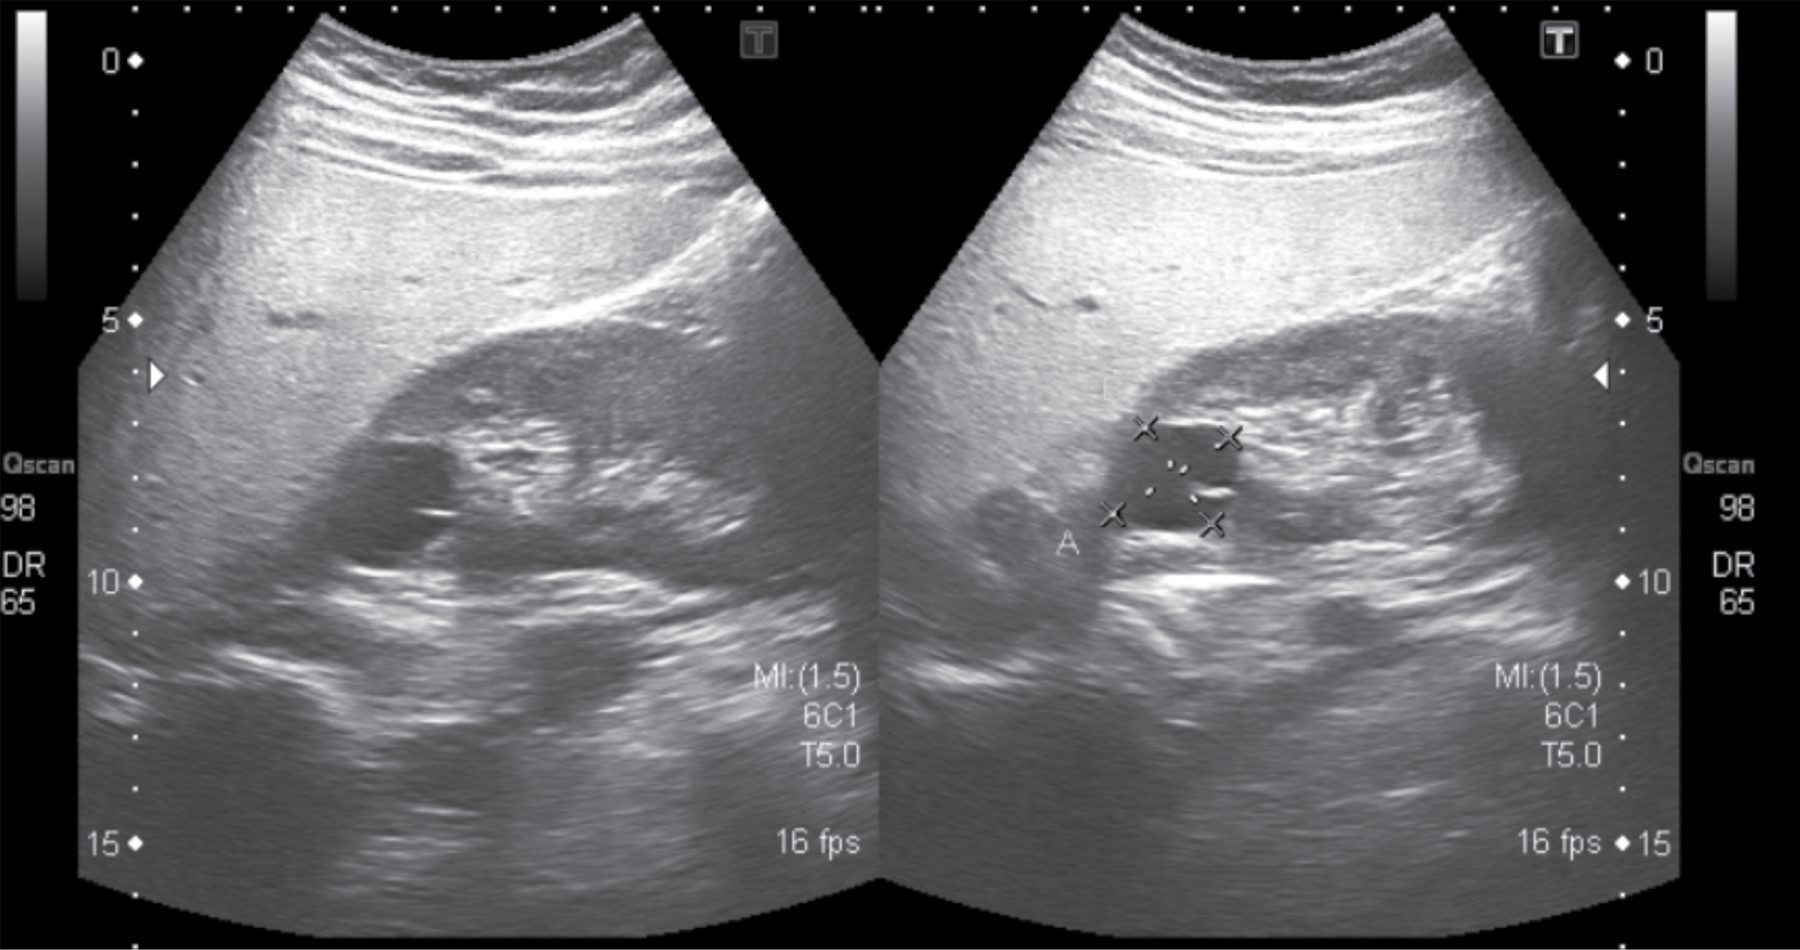

Objective: The presence of mutations in the HNF1β gene is associated with diabetes, renal and genital malformations, as well as electrolyte disorders. The clinical presentation varies with the age of onset of symptoms. Case presentation: We report the evolution of two pediatric patients with this entity who began their follow-up due to a renal malformation. As the study continued, more manifestations were added that led to the diagnosis suspicion. Diagnosis was confirmed by molecular study (Multiplex Ligation-dependent Probe Amplification). The first case is an 11-year-old female patient, who was detected prenatally with a multicystic kidney; during her follow-up hypomagnesaemia (4 years old) was identified. During puberty, alterations in the lipid and liver profiles, as well as agenesis of the right ovary were demonstrated. The second case is a 17-year-old male, with a prenatal diagnosis of left pyelocalyceal dilation. At three years of age, a right renal cyst was detected and, at 13 years, diabetes and hepatic steatosis. In both cases, when carrying out a molecular study, a mutation was detected in the HNF1β gene. Conclusions: In pediatric age, the search for mutations in the HNF1β gene should be taken into account in patients with renal malformations, who have other clinical manifestations such as diabetes or electrolyte disorders.

Figure 1

Figure 2